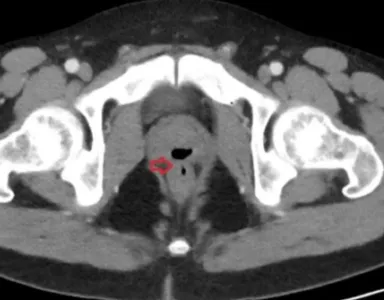

Outros exames identificaram fústula — uma passagem anormal — entre a uretra e o reto, por onde fluidos corriam. O homem foi submetido a uma cirurgia. Os médicos descobriram, também, que, quando esteve em coma, o paciente recebeu um cateter que poderia ter causado as complicações. O caso foi registrado na revista científica Cureus.